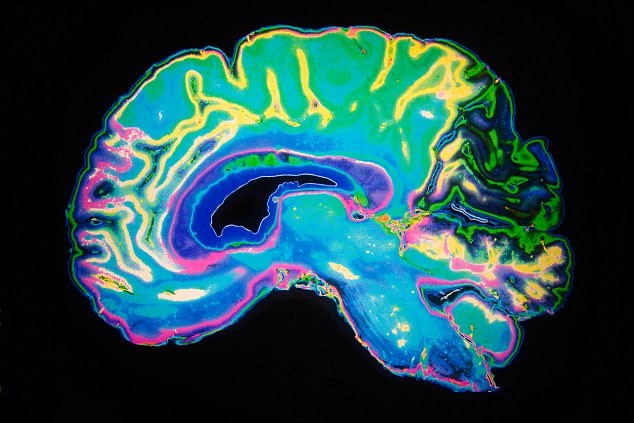

Một bức ảnh fMRI. Ảnh: Alamy Stock Photo

Ảnh chụp cộng hưởng từ chức năng cung cấp một bản đồ của hoạt động não, bằng cách nhận diện sự thay đổi trong lưu lượng máu khi máu được di chuyển đến các vùng não cụ thể.